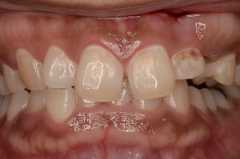

部分矯正とセラミックのハイブリット矯正にて治療例

上顎の前歯の部分矯正とセラミックを3本にて治療を行っています。